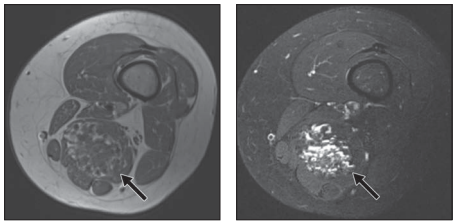

En este trabajo del American Jornal of Roentgenology se presenta una lista de 8 pasos a tener en cuenta al momento de describir una lesión tumoral de partes blandas, con el propósito principal de excluir una lesión maligna o sarcomatosa.

4. Posee áreas prominentes de baja señal en T2?

De esta manera, al responder sobre cada lesión las preguntas antes citadas, se podrá tener una aproximación al origen de la lesión, descartar ciertas alteraciones y proponer algunos diagnósticos diferenciales. Dado que la mayoría de las lesiones serán estudiadas anatomopatológicamente el radiólogo puede indicar cual es el sitio de la lesión más apropiado para obtener un rédito diagnóstico.